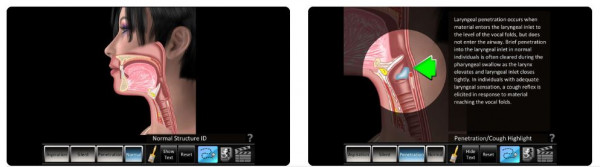

The Aspiration Disorders app has features to help health professionals teach patients about aspiration swallowing disorders. The app has animated drawings and video recordings of swallows (MBS and FEES) to illustrate what happens during normal swallowing and during aspiration disorders. Aspiration happens when food or liquids enter the airway, either during a swallow or when food comes back up from the stomach. It can cause coughing and choking and if the aspirated contents reach the lungs, it can cause a serious condition called aspiration pneumonia. Aspiration disorders are more likely in people who have swallowing difficulties.

The language and illustrations in this app are quite technical. Consequently it is unlikely to have any benefit to consumers if used outside of a consultation with a speech language therapist. For the complete app description, go to the app website(external link), App Store(external link), Play Store(external link), or for a more detailed review, see reviews below.

✔ Pictures and videos of 4 different swallows: normal (no food/drink entered the airway), aspiration (entered the airway), silent (entered the airway without a cough), and penetration/cough (stops just short of entering the airway). ✔ There is a text description for each swallow describing what is happening. |

✘ Extremely poor readability. The app description says it is targeted to both students and patients. However, it uses very high-level medical language which would require prior medical training to understand. It has a Flesch readability score of 22 (scale is 0 to 100, with 0 being very confusing/difficult, and 100 being very easy). The app is unlikely to be useful to anyone unless used with a speech language therapist. ✘ Anatomical drawings and videos aren't labelled. |

Comments: This app would only be useful if used during a consultation or discussion with a speech language therapist. The anatomical illustrations and videos could be useful to visualise what is happening during a normal swallow versus a swallow with penetration or aspiration occurring. However, without a trained professional the app has very limited use. It has no benefit post diagnosis for dysphagia rehab or management and the information contained in the app is highly medical with no glossary.